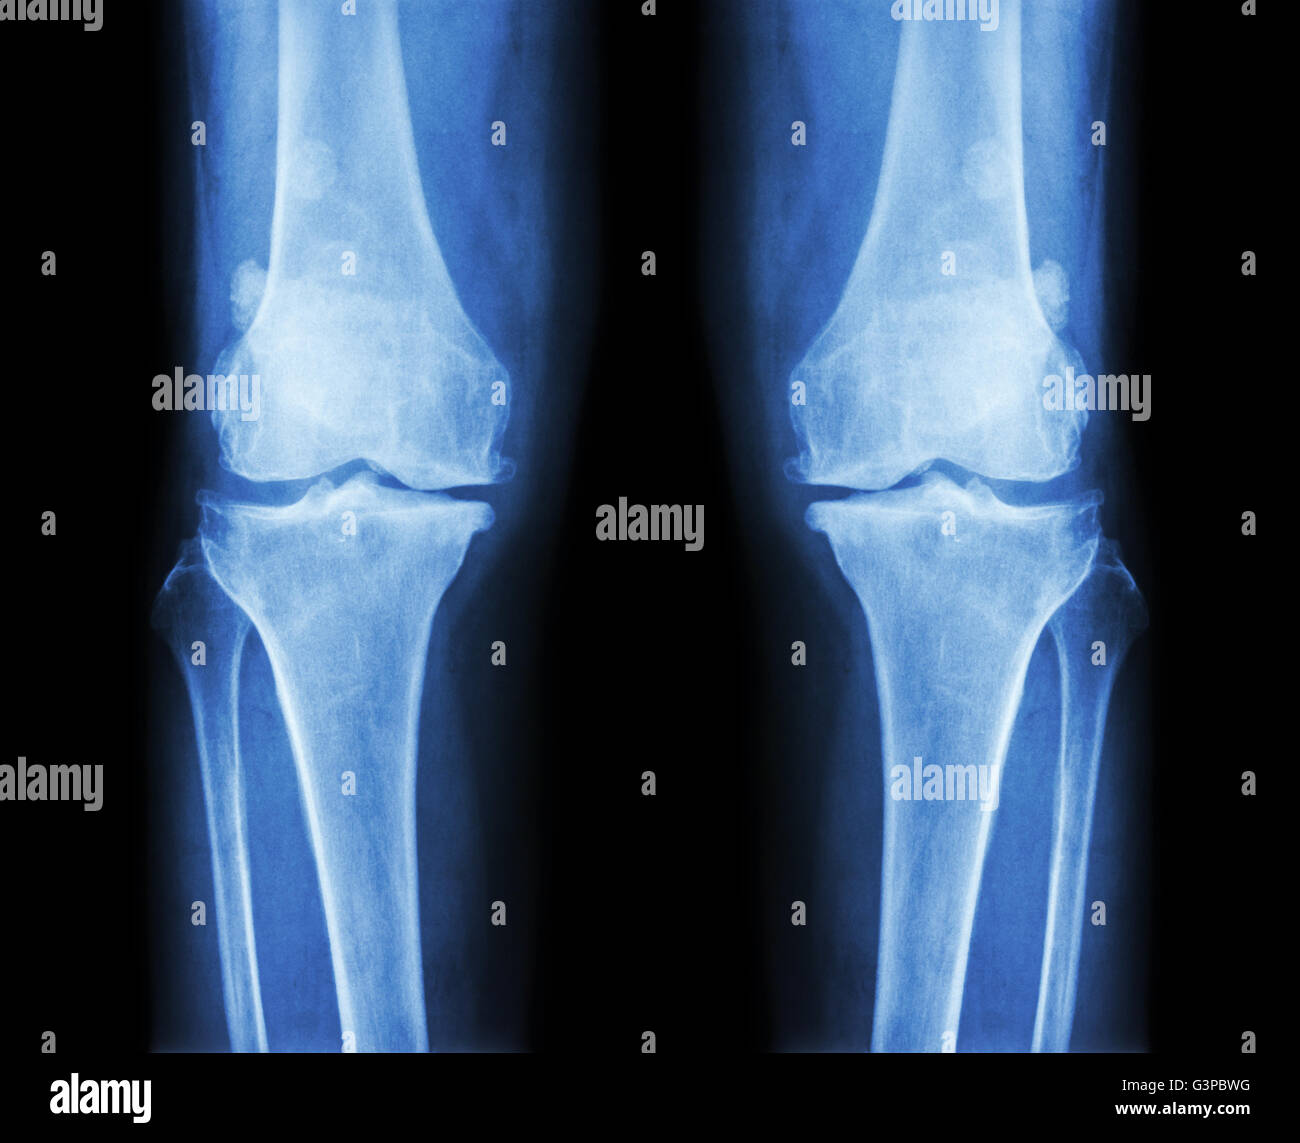

L'ARTHROSE DU GENOU Arthrose du genou ( ). Film x-ray deux genou ( vue avant ) show spatial commun étroit ( perte de cartilage ) , osteophy Banque D'Imageshttps://www.alamyimages.fr/image-license-details/?v=1https://www.alamyimages.fr/photo-image-l-arthrose-du-genou-arthrose-du-genou-film-x-ray-deux-genou-vue-avant-show-spatial-commun-etroit-perte-de-cartilage-osteophy-87802628.html

L'ARTHROSE DU GENOU Arthrose du genou ( ). Film x-ray deux genou ( vue avant ) show spatial commun étroit ( perte de cartilage ) , osteophy Banque D'Imageshttps://www.alamyimages.fr/image-license-details/?v=1https://www.alamyimages.fr/photo-image-l-arthrose-du-genou-arthrose-du-genou-film-x-ray-deux-genou-vue-avant-show-spatial-commun-etroit-perte-de-cartilage-osteophy-87802628.htmlRFF2RN44–L'ARTHROSE DU GENOU Arthrose du genou ( ). Film x-ray deux genou ( vue avant ) show spatial commun étroit ( perte de cartilage ) , osteophy

L'ARTHROSE DU GENOU Arthrose du genou ( ). Film x-ray deux genou ( vue avant ) show spatial commun étroit ( perte de cartilage ) , osteophy Banque D'Imageshttps://www.alamyimages.fr/image-license-details/?v=1https://www.alamyimages.fr/photo-image-l-arthrose-du-genou-arthrose-du-genou-film-x-ray-deux-genou-vue-avant-show-spatial-commun-etroit-perte-de-cartilage-osteophy-87802655.html

L'ARTHROSE DU GENOU Arthrose du genou ( ). Film x-ray deux genou ( vue avant ) show spatial commun étroit ( perte de cartilage ) , osteophy Banque D'Imageshttps://www.alamyimages.fr/image-license-details/?v=1https://www.alamyimages.fr/photo-image-l-arthrose-du-genou-arthrose-du-genou-film-x-ray-deux-genou-vue-avant-show-spatial-commun-etroit-perte-de-cartilage-osteophy-87802655.htmlRFF2RN53–L'ARTHROSE DU GENOU Arthrose du genou ( ). Film x-ray deux genou ( vue avant ) show spatial commun étroit ( perte de cartilage ) , osteophy

L'ARTHROSE DU GENOU Arthrose du genou ( ). Film x-ray deux genou ( vue avant ) show spatial commun étroit ( perte de cartilage ) , osteophy Banque D'Imageshttps://www.alamyimages.fr/image-license-details/?v=1https://www.alamyimages.fr/photo-image-l-arthrose-du-genou-arthrose-du-genou-film-x-ray-deux-genou-vue-avant-show-spatial-commun-etroit-perte-de-cartilage-osteophy-87802612.html

L'ARTHROSE DU GENOU Arthrose du genou ( ). Film x-ray deux genou ( vue avant ) show spatial commun étroit ( perte de cartilage ) , osteophy Banque D'Imageshttps://www.alamyimages.fr/image-license-details/?v=1https://www.alamyimages.fr/photo-image-l-arthrose-du-genou-arthrose-du-genou-film-x-ray-deux-genou-vue-avant-show-spatial-commun-etroit-perte-de-cartilage-osteophy-87802612.htmlRFF2RN3G–L'ARTHROSE DU GENOU Arthrose du genou ( ). Film x-ray deux genou ( vue avant ) show spatial commun étroit ( perte de cartilage ) , osteophy

L'ARTHROSE DU GENOU Arthrose du genou ( ). Film x-ray deux genou ( vue avant ) show spatial commun étroit ( perte de cartilage ) , osteophy Banque D'Imageshttps://www.alamyimages.fr/image-license-details/?v=1https://www.alamyimages.fr/photo-image-l-arthrose-du-genou-arthrose-du-genou-film-x-ray-deux-genou-vue-avant-show-spatial-commun-etroit-perte-de-cartilage-osteophy-87802643.html

L'ARTHROSE DU GENOU Arthrose du genou ( ). Film x-ray deux genou ( vue avant ) show spatial commun étroit ( perte de cartilage ) , osteophy Banque D'Imageshttps://www.alamyimages.fr/image-license-details/?v=1https://www.alamyimages.fr/photo-image-l-arthrose-du-genou-arthrose-du-genou-film-x-ray-deux-genou-vue-avant-show-spatial-commun-etroit-perte-de-cartilage-osteophy-87802643.htmlRFF2RN4K–L'ARTHROSE DU GENOU Arthrose du genou ( ). Film x-ray deux genou ( vue avant ) show spatial commun étroit ( perte de cartilage ) , osteophy